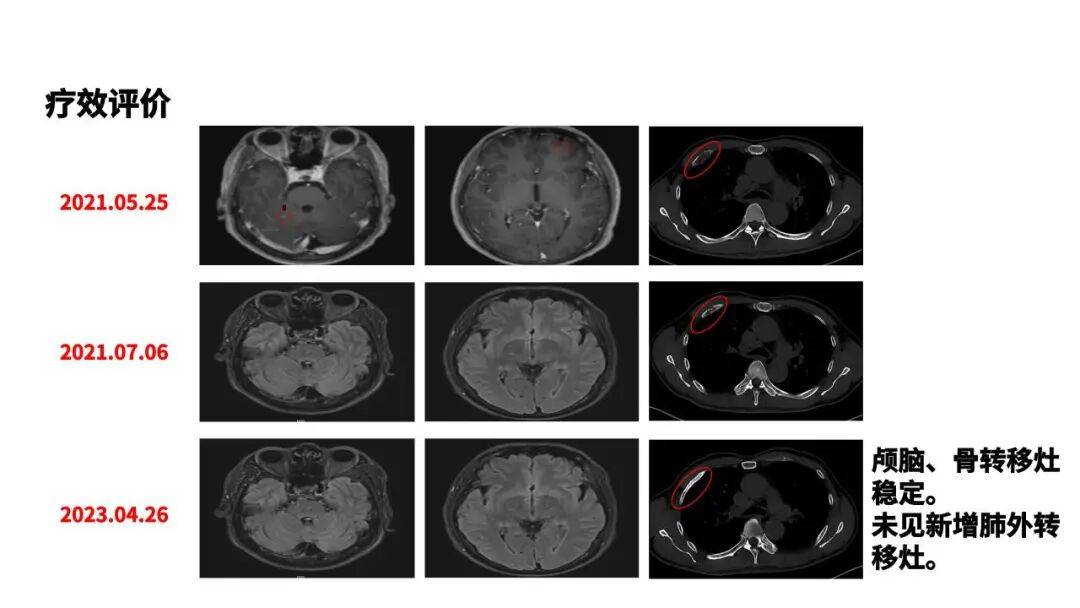

本例患者肿瘤异质性强,基线合并有脑转移、携带EGFR L858R突变、TP53突变以及PD-L1表达弱阳性等诸多预后不良因素。基于指南推荐[1],一线治疗为患者选用了伏美替尼。临床研究数据也为该治疗方案提供了有力佐证,FURLONG研究[2,3]显示,伏美替尼一线治疗EGFR敏感突变可显著延长患者PFS至20.8个月,对基线有脑转移患者效果亦明显,且安全性良好,正契合该患者需求。治疗后,该例患者疗效评估为PR,PFS达到了23个月,且颅脑转移灶稳定,且该例患者在接受长期治疗过程中未出现不良反应。但该例患者随后出现缓慢进展,更强效的联合治疗方案或能突破瓶颈,遂加用安罗替尼,结果显示亦获得优秀疗效,联合治疗9周期后疗效达SD。但随着治疗时间的拉长,EGFR-TKI耐药情况难以避免,为延长患者生存期并提高生活质量,如何调整后续治疗方案至关重要。